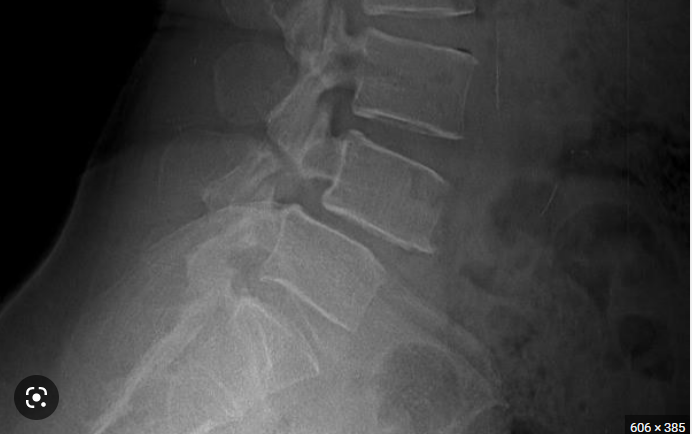

Theo tác giả Meyerding, trượt đốt sống được chia thành 5 mức độ. Mức độ trượt được xác định bằng tỉ lệ dựa trên phim X-quang quy ước ở tư thế nghiêng. Tỷ lệ trượt được tính bằng khoảng cách trượt với độ rộng của thân đốt sống trượt. 5 độ của trượt đốt sống:

- Độ 1: Trượt 0 - 25% thân đốt sống.

- Độ 2: Trượt 26 - 50% thân đốt sống.

- Độ 3: Trượt 51 - 75% thân đốt sống.

- Độ 4: Trượt 76 - 100% thân đốt sống.

- Độ 5: Trượt hoàn toàn, đốt trên hoàn toàn rời khỏi bề mặt thân đốt dưới.

- Chụp X-quang ở các tư thế: Thẳng, nghiêng, cúi tối đa và ưỡn tối đa. Trong một số trường hợp, cần thiết chụp thêm film chếch 3⁄4 (phải, trái). X-quang quy ước giúp chẩn đoán chính xác vị trí trượt, mức độ trượt.